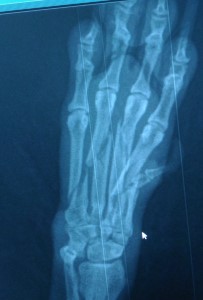

перелом пясти и пальцев у собаки

Для установления локализации перелома необходимо проведение рентген-диагностики.  Хирург, проведя осмотр вашего питомца и получив результаты рентгенографии, оценивает сложность перелома, разрабатывает тактику лечения. Часто при переломах одного пальца, если не произошло смещения отломков, хирургическое лечение не требуется, достаточно на короткое время иммобилизировать конечность, и перелом срастется самостоятельно.